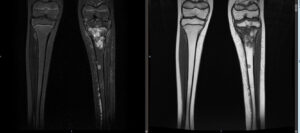

- Ressonância Magnética (RM): Fornece detalhes sobre a extensão do tumor e sua relação com os tecidos moles ao redor.

- Tomografia Computadorizada (TC): Ajuda a avaliar a extensão do tumor, especialmente nos ossos.